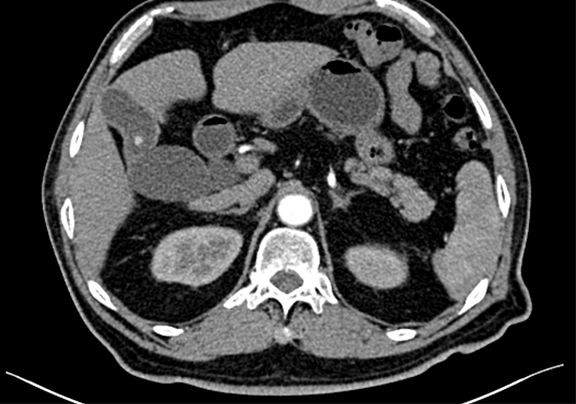

静脉期